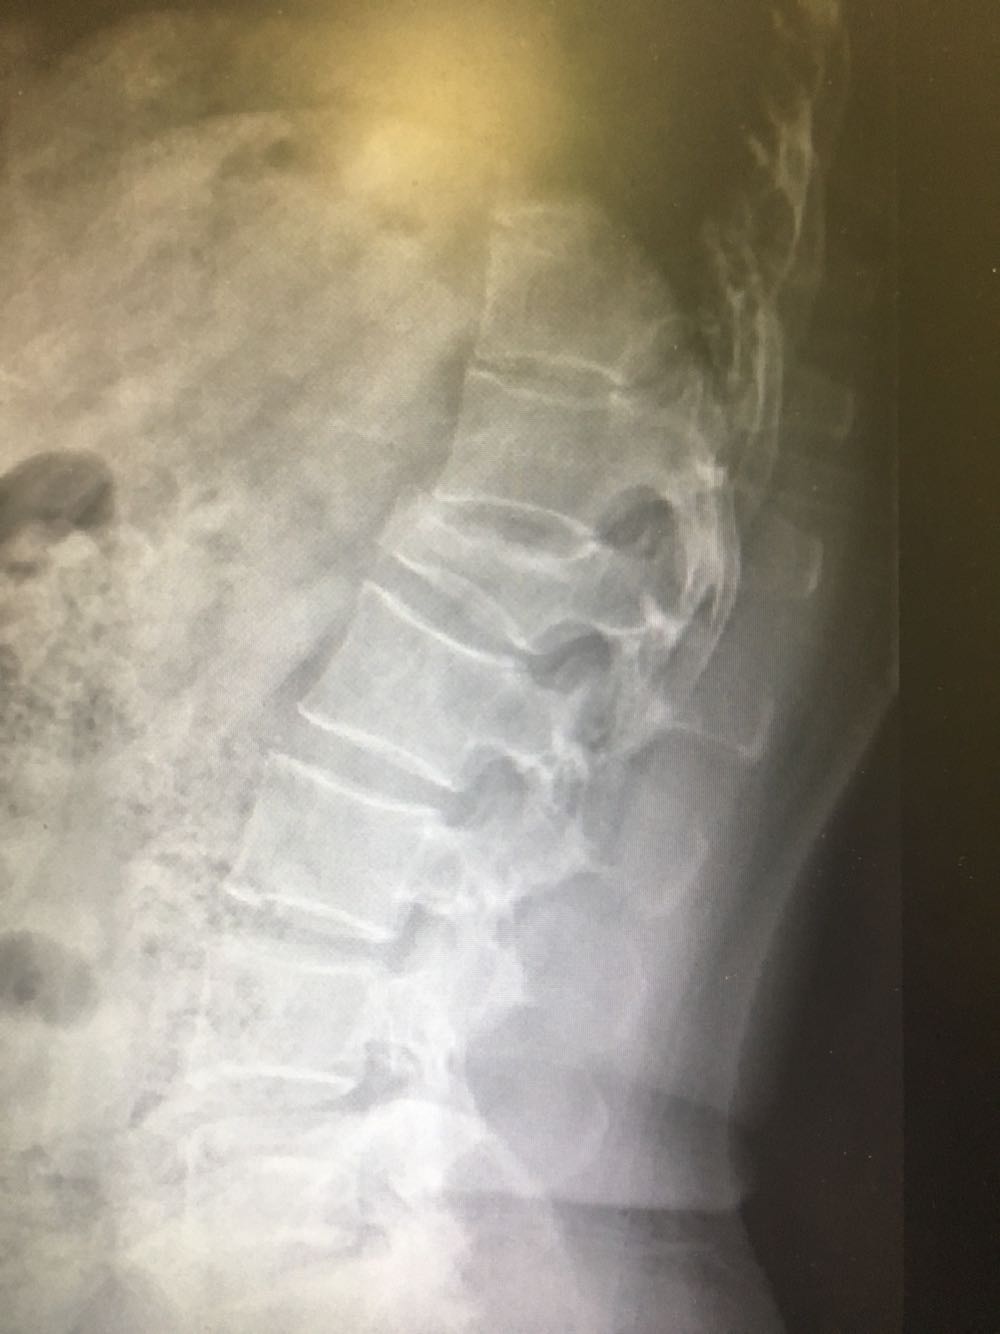

患者,女性,54岁 主诉:摔伤致腰背疼痛伴活动受限3小时 现病史:患者于3小时前于摔倒致腰背疼痛伴活动受限,患者诉站立及坐位时腰痛加剧,卧床时可缓解,否认头晕头痛、恶心呕吐等不适,遂至我院就诊,查X片示:腰椎L1压缩性骨折,现为进一步诊治收治入院,发病以来,神清,精神可,胃纳夜眠可,二便无殊,体重无明显变化。

查体:脊柱无侧弯、畸形,腰段压痛及叩击痛阳性,下肢肌力肌张力正常,运动及感觉正常。 辅检:见现病史

诊断:腰椎骨折(L1) 治疗:完善术前检查后行手术治疗